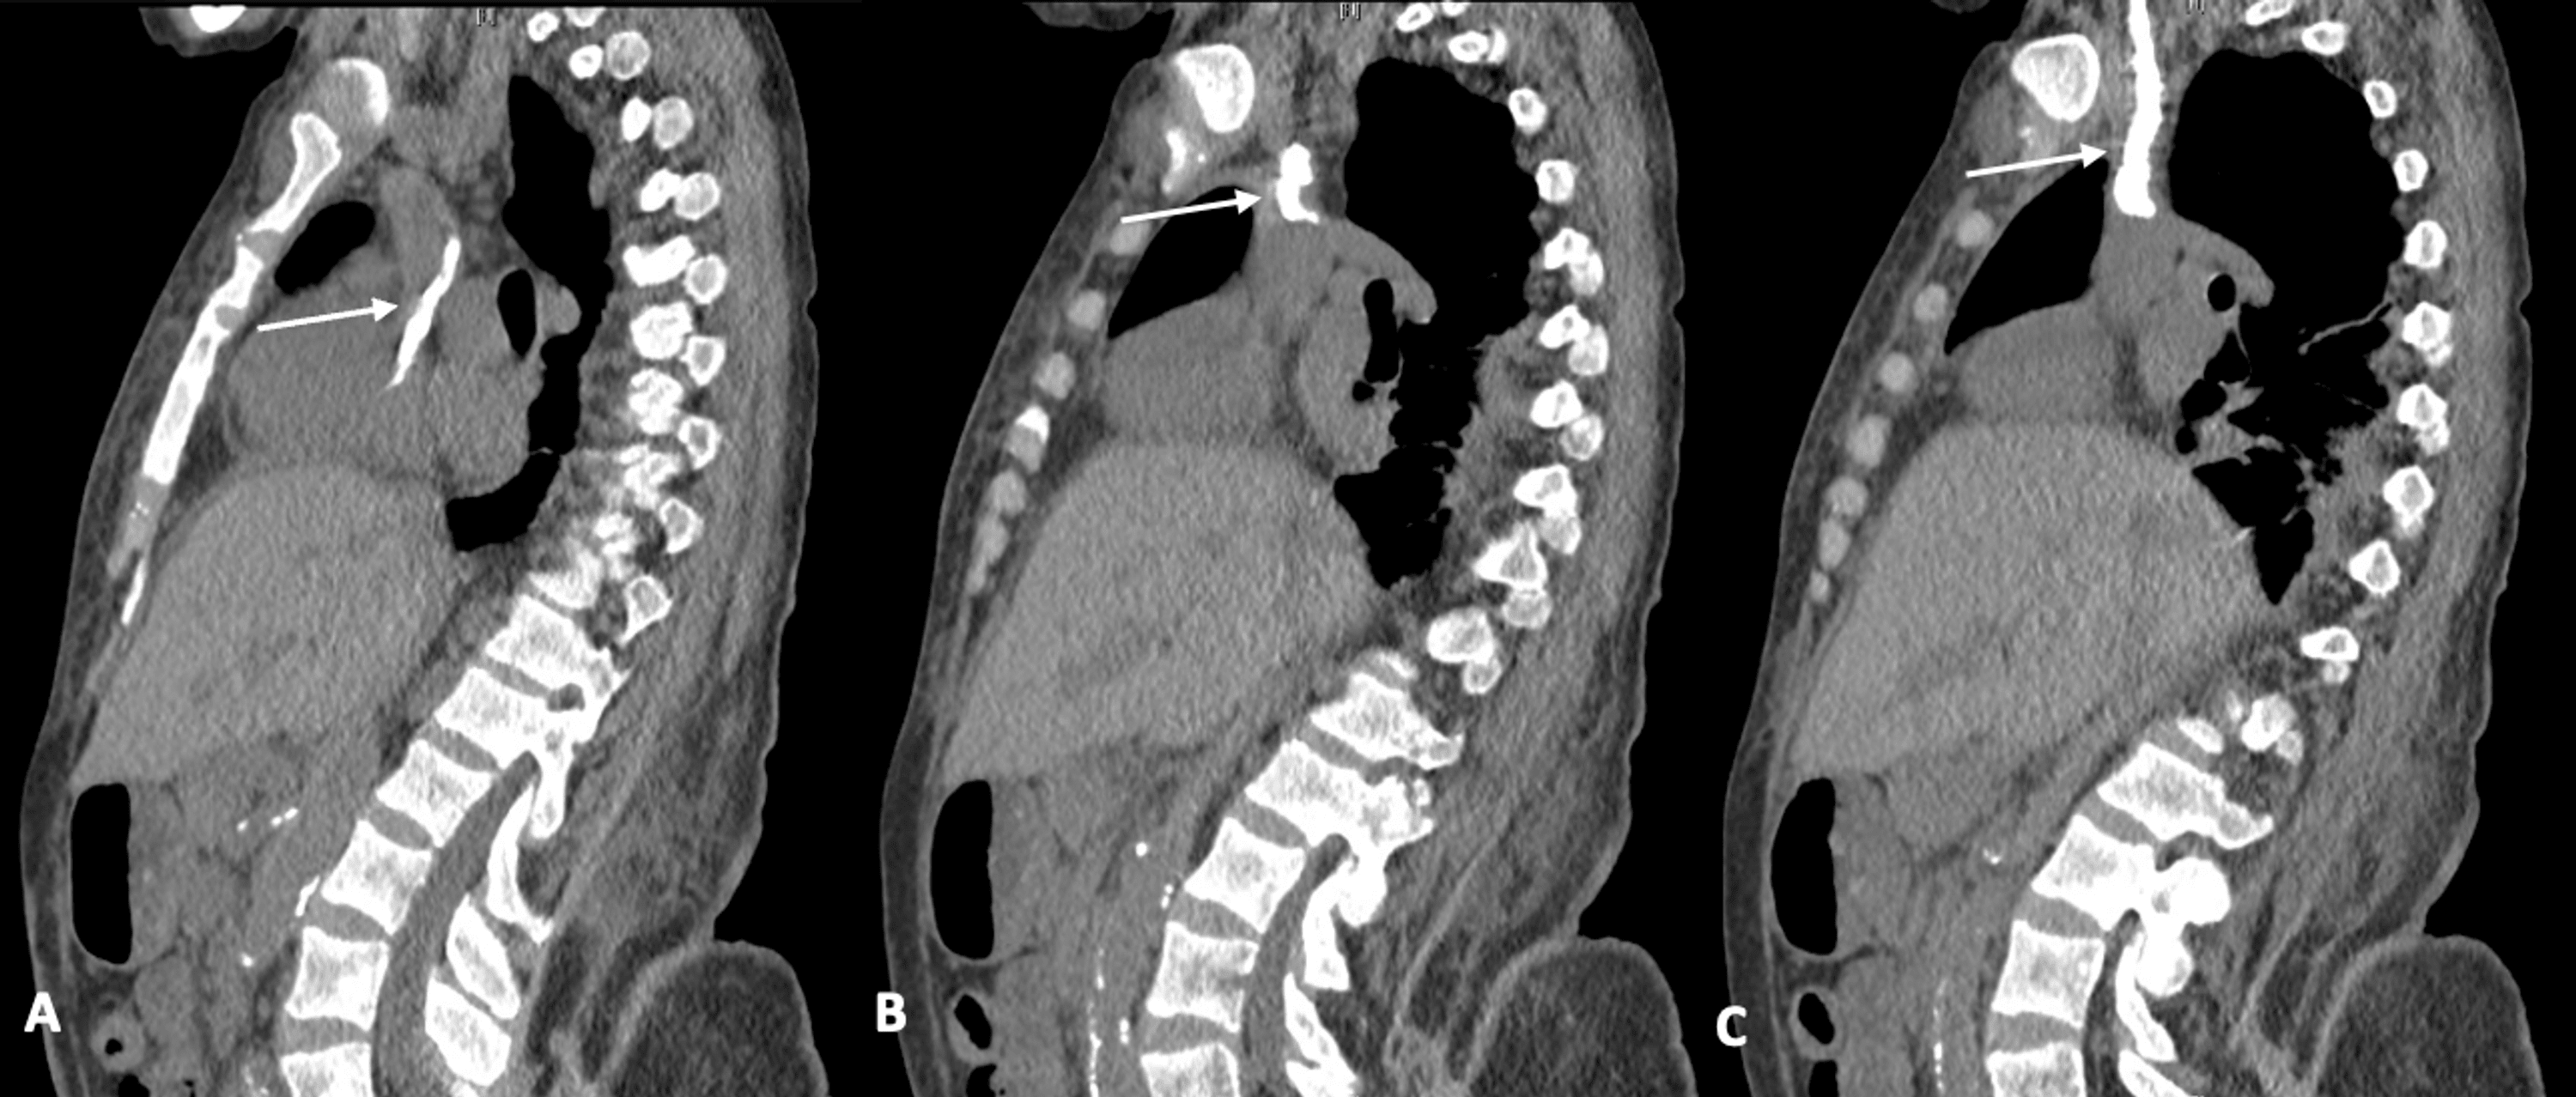

Fibrin sheath along the catheter lumen (arrows) and bulging at the Hemodialysis Catheter Fibrin Sheath One unique problem for catheters is the formation of fibrin sheaths. Case 3 suggests the presence of a fibrin sheath, which can begin to form as soon as 24 hours following placement of the catheter. A fibrin sheath is composed of fibrinogen,. A fibrin sheath (imagine a structure similar to a sword’s sheath) can completely envelop a cvc and obstruct. Hemodialysis Catheter Fibrin Sheath.

(PDF) Calcified CatheterRelated Fibrin Sheath Forms Large Intravenous Hemodialysis Catheter Fibrin Sheath Fibrin sheath formation is a primary cause of cvc malfunction, with up to 50% of hemodialysis patients experiencing fibrin. Case 3 suggests the presence of a fibrin sheath, which can begin to form as soon as 24 hours following placement of the catheter. A fibrin sheath (imagine a structure similar to a sword’s sheath) can completely envelop a cvc and. Hemodialysis Catheter Fibrin Sheath.

Calcified CatheterRelated Fibrin Sheath Forms Large Intravenous Cast Hemodialysis Catheter Fibrin Sheath Case 3 suggests the presence of a fibrin sheath, which can begin to form as soon as 24 hours following placement of the catheter. A fibrin sheath is composed of fibrinogen,. Fibrin sheath formation is a primary cause of cvc malfunction, with up to 50% of hemodialysis patients experiencing fibrin. A fibrin sheath (imagine a structure similar to a sword’s. Hemodialysis Catheter Fibrin Sheath.